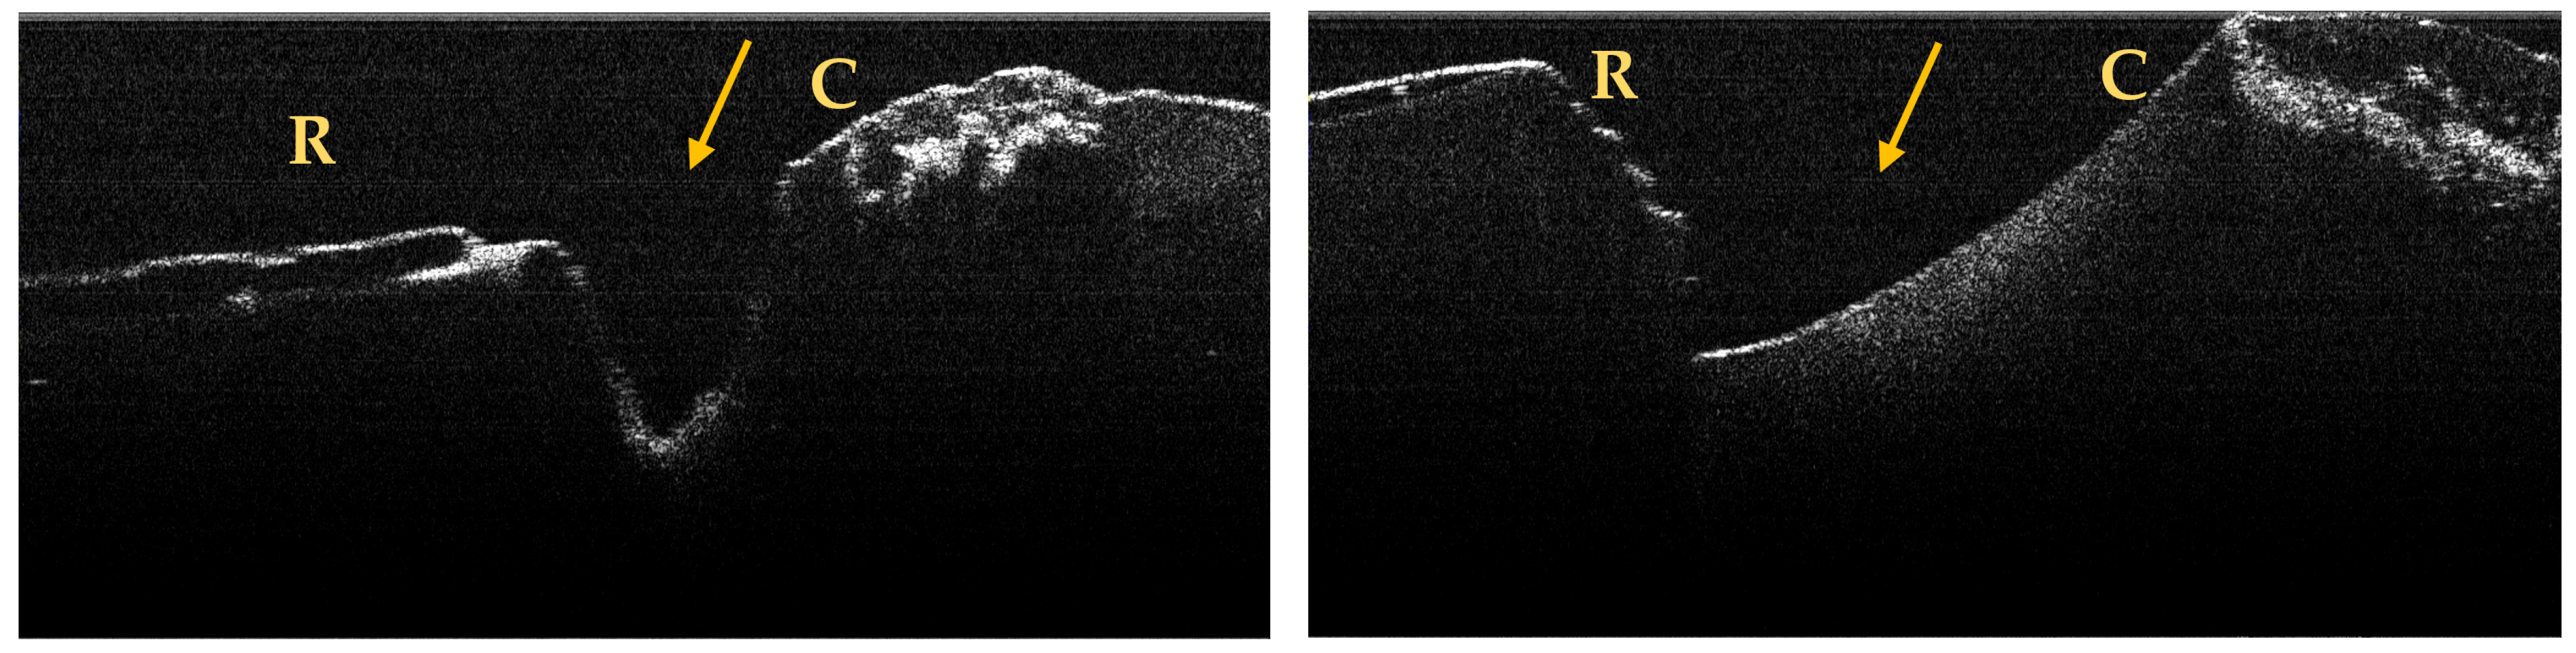

A maximum of 512 OCT images was taken for each dental surface examined. Figure 3, Figure 4 and Figure 5 present specific OCT images of teeth with macroscopically identified NCCLs, but also specific OCT images of teeth in which the NCCLs were not visible macroscopically. In each figure depicting the OCT images obtained, the position of the dental crown is marked with the letter C, the position of the root is marked with the letter R, and the arrow indicates the NCCL.

Figure 3.

OCT images of a wedge-shaped NCC, indicated by the arrows.

Figure 4.

OCT images of a saucer-shaped NCCL, indicated by the arrows.